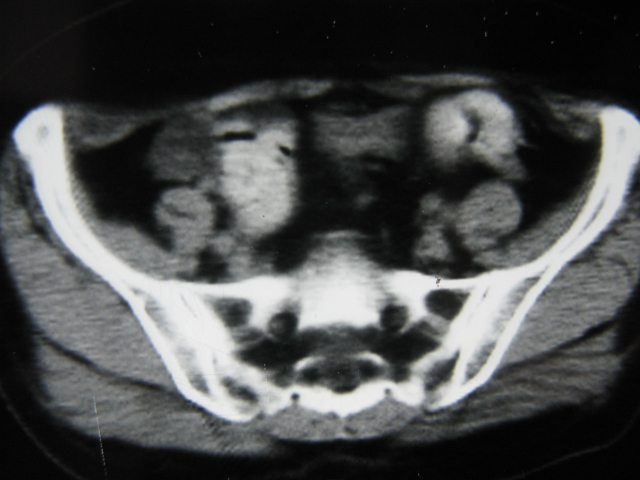

患者,女,64岁,2002年诊断为宫颈癌,当时只做过放,化疗。现在诊断:(1)宫颈癌。(2)直肠癌。请同道们讨论,探讨。另外肠壁为啥密度这么高,ct值约112hu。患者没有做过增强和造影。

高密度的不是肠管影,是肠管内的粪便影

患者直肠病变,排便不畅,粪便硬结造成,更高密度如钡灌肠者都可出现

硬结粪便能有如此高密度影?

我也碰到过几例,最离奇的一例是全结肠呈造影样高密度,患者直肠癌(首次发现),以往没有吃药,只有约半年时间长的胃纳差,排便不畅(据患者说每次大便只能拉出少许黄水)

不一定有意义,可清洁灌肠后复查